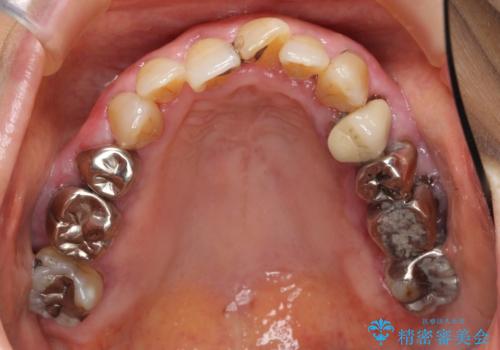

歯ぐきから血が出る、歯ぐきが腫れている 80代女性

- 歯ぐきからの出血と腫れを主訴に来院された患者様です。

プラークコントロールが非常に悪く、全顎的な歯周病に罹患していました。

「抜歯したくない、インプラントは嫌」という患者様のご希望とご年齢を考慮し、可及的な骨外科処置や根分割術によりできるだけ今ある歯を残す治療方針をたてました。

保存不可能な左上の奥歯2本(左上67)は抜去し、ノンクラスプデンチャーをいれることにしました。

長期的な予後は保証できないことをご了承頂いた上で治療を行いました。